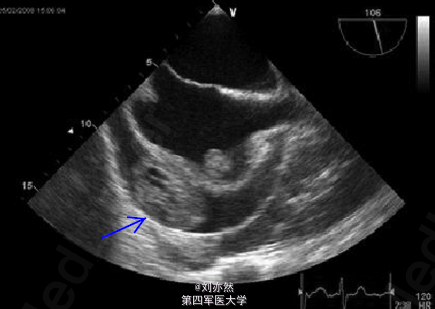

心脏血管肉瘤两例

一例经食管心动超声示:血管肉瘤位于心包内,并浸润心房壁(图1)。一例MRI示肿块位于心包内,邻近下腔静脉及右心房,并造成心包积液(图2)。 讨论:心脏原发性肿瘤极少见,其中肉瘤为最常见的类型。影像学检查结合病理学检查确诊病例。 引自:Beraldo DO, Melo JF et al. World J Gastroenterol. 2013 Dec 14;19(46):8789-92.